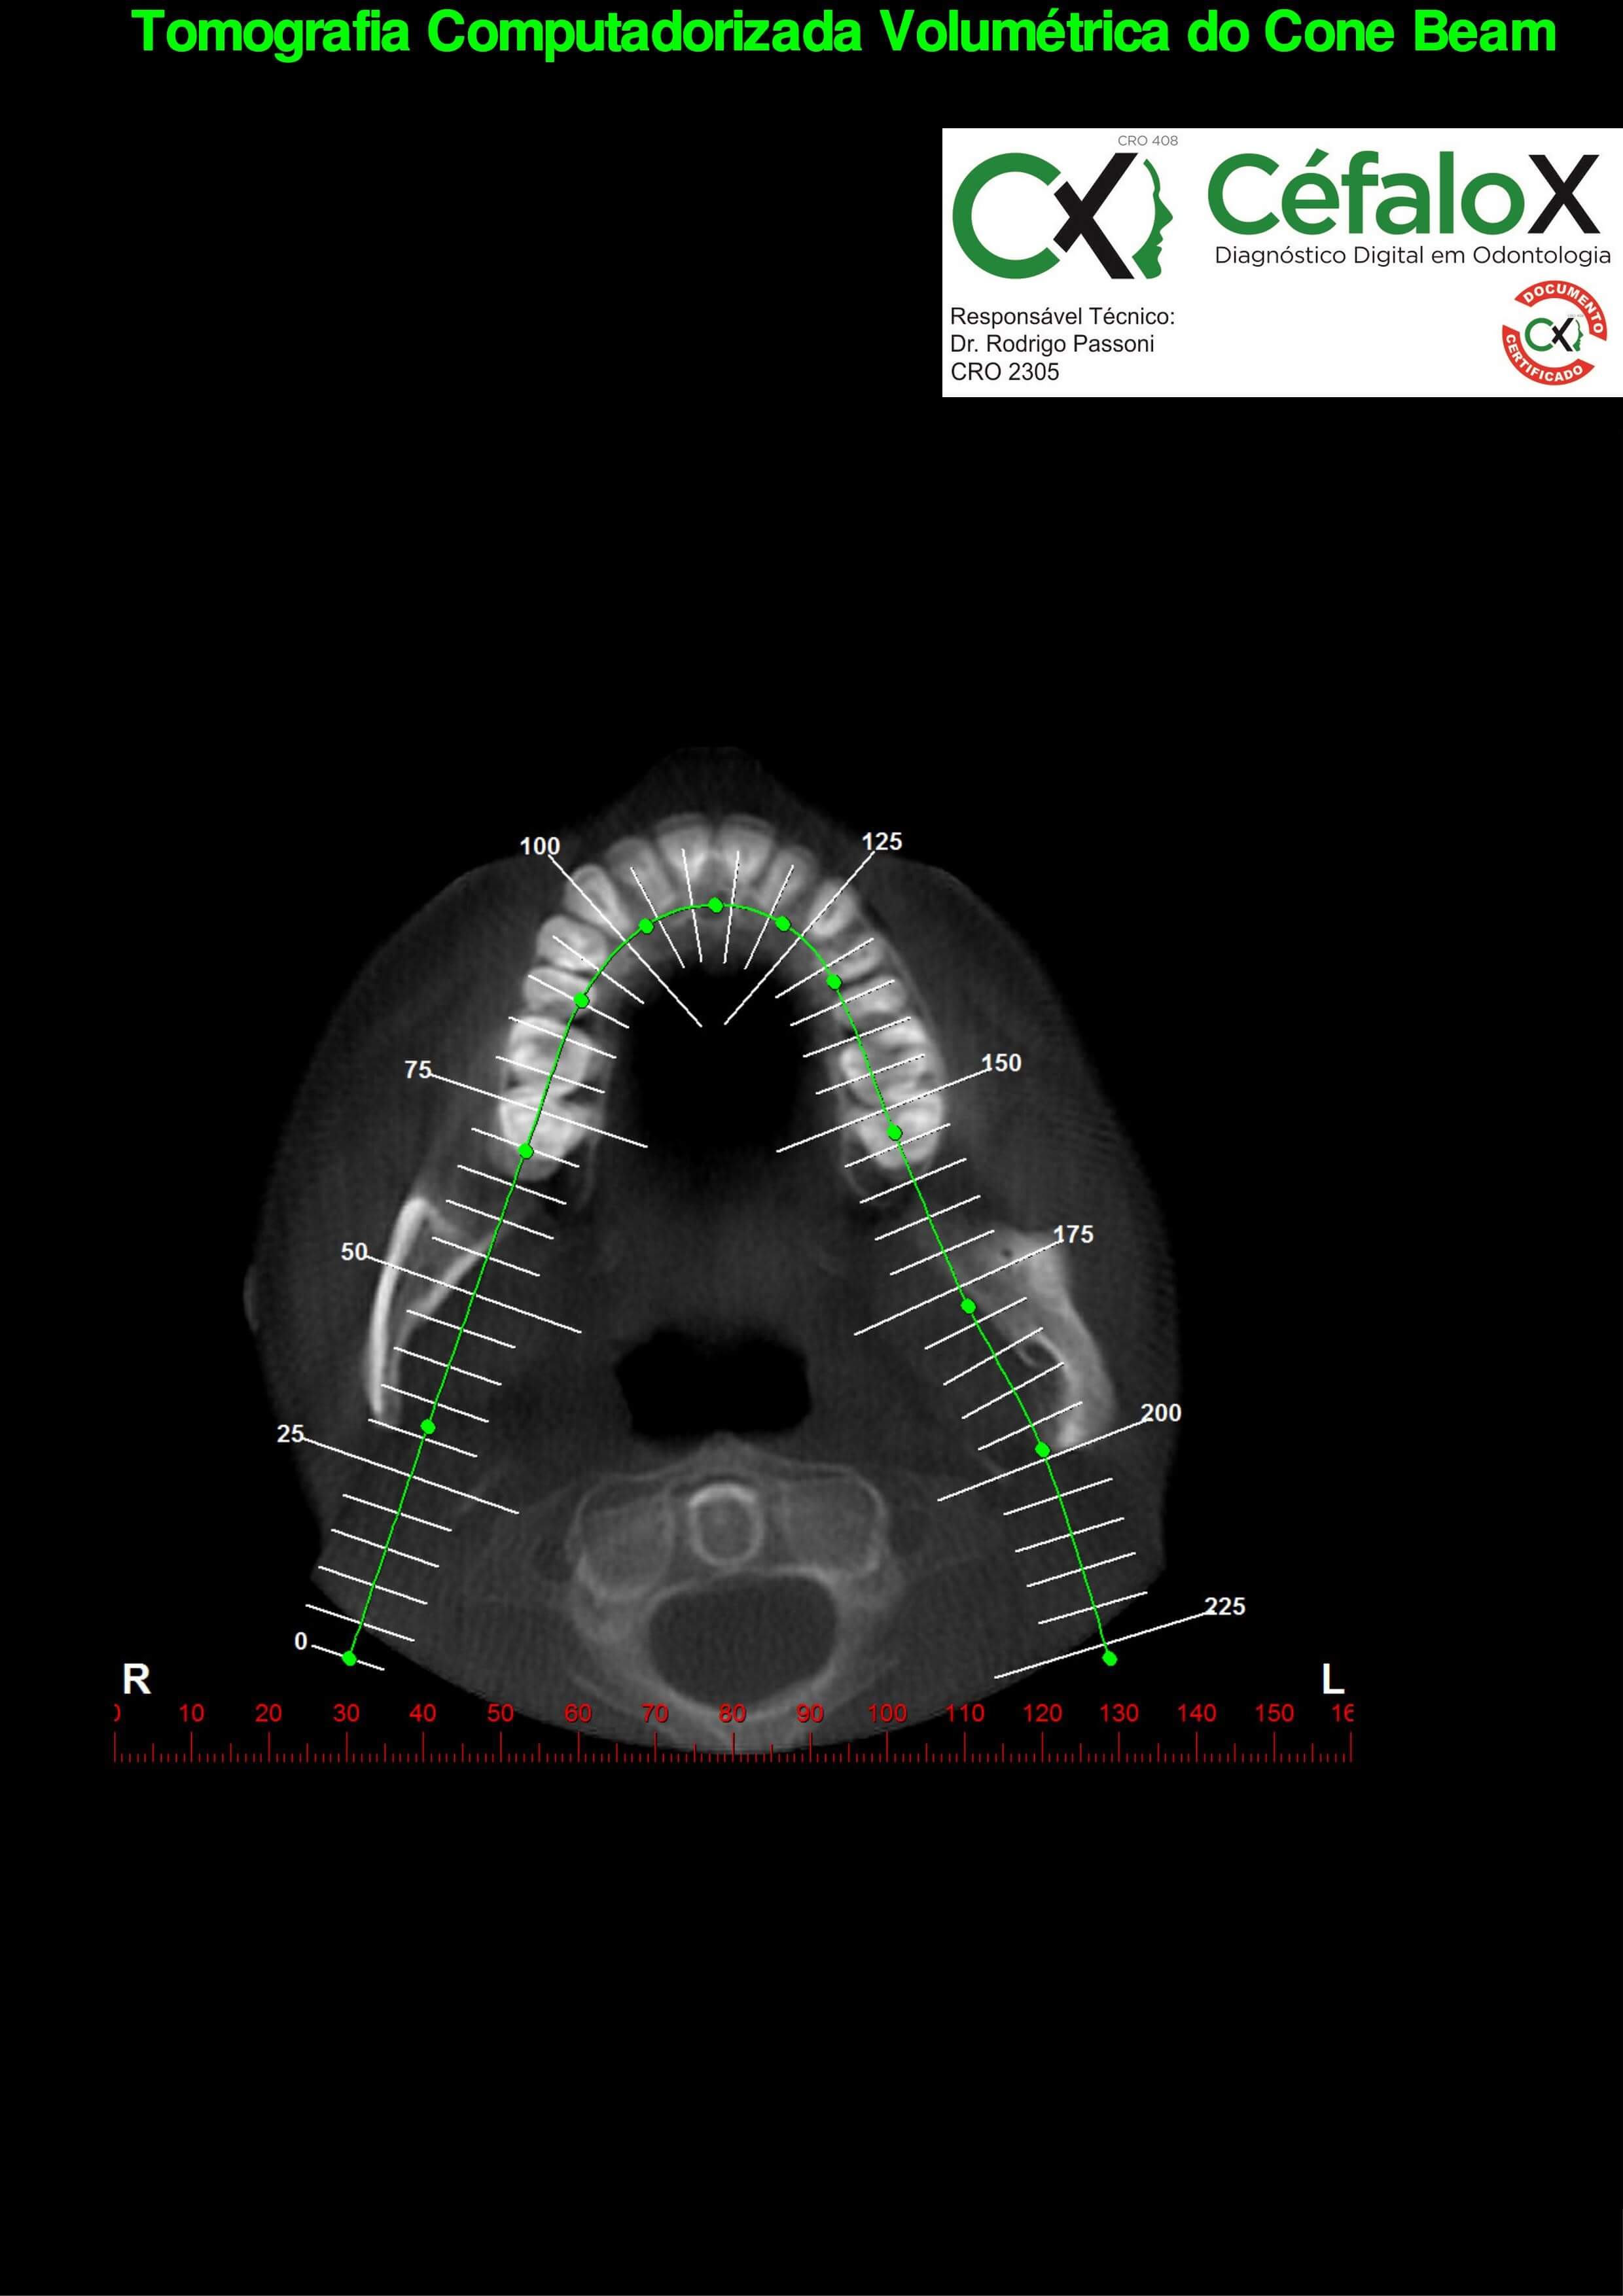

TC de face (do Hióide à Glabela), reconstrução 3D do tecido ósseo, radiografia panorâmica, telerradiografia lateral com traçado, cortes transversais e axial de maxila e mandíbula e arquivo DICOM- entregue em pasta de Pvc.

TC de face (do Hióide à Glabela), reconstrução 3D do tecido ósseo, radiografia panorâmica, telerradiografia lateral e frontal com traçado, cortes transversais e axial de maxila/mandíbula e arquivo DICOM – entregue em pasta de Pvc.

TC de face (do Hióide à Glabela), reconstruções 3D do tecido mole/ósseo/vias aéreas, radiografia panorâmica, telerradiografia lateral e frontal com traçado, cortes transversais e axial de maxila/mandíbula, ATM e arquivo DICOM – entregue em pasta e caixa de Pvc.